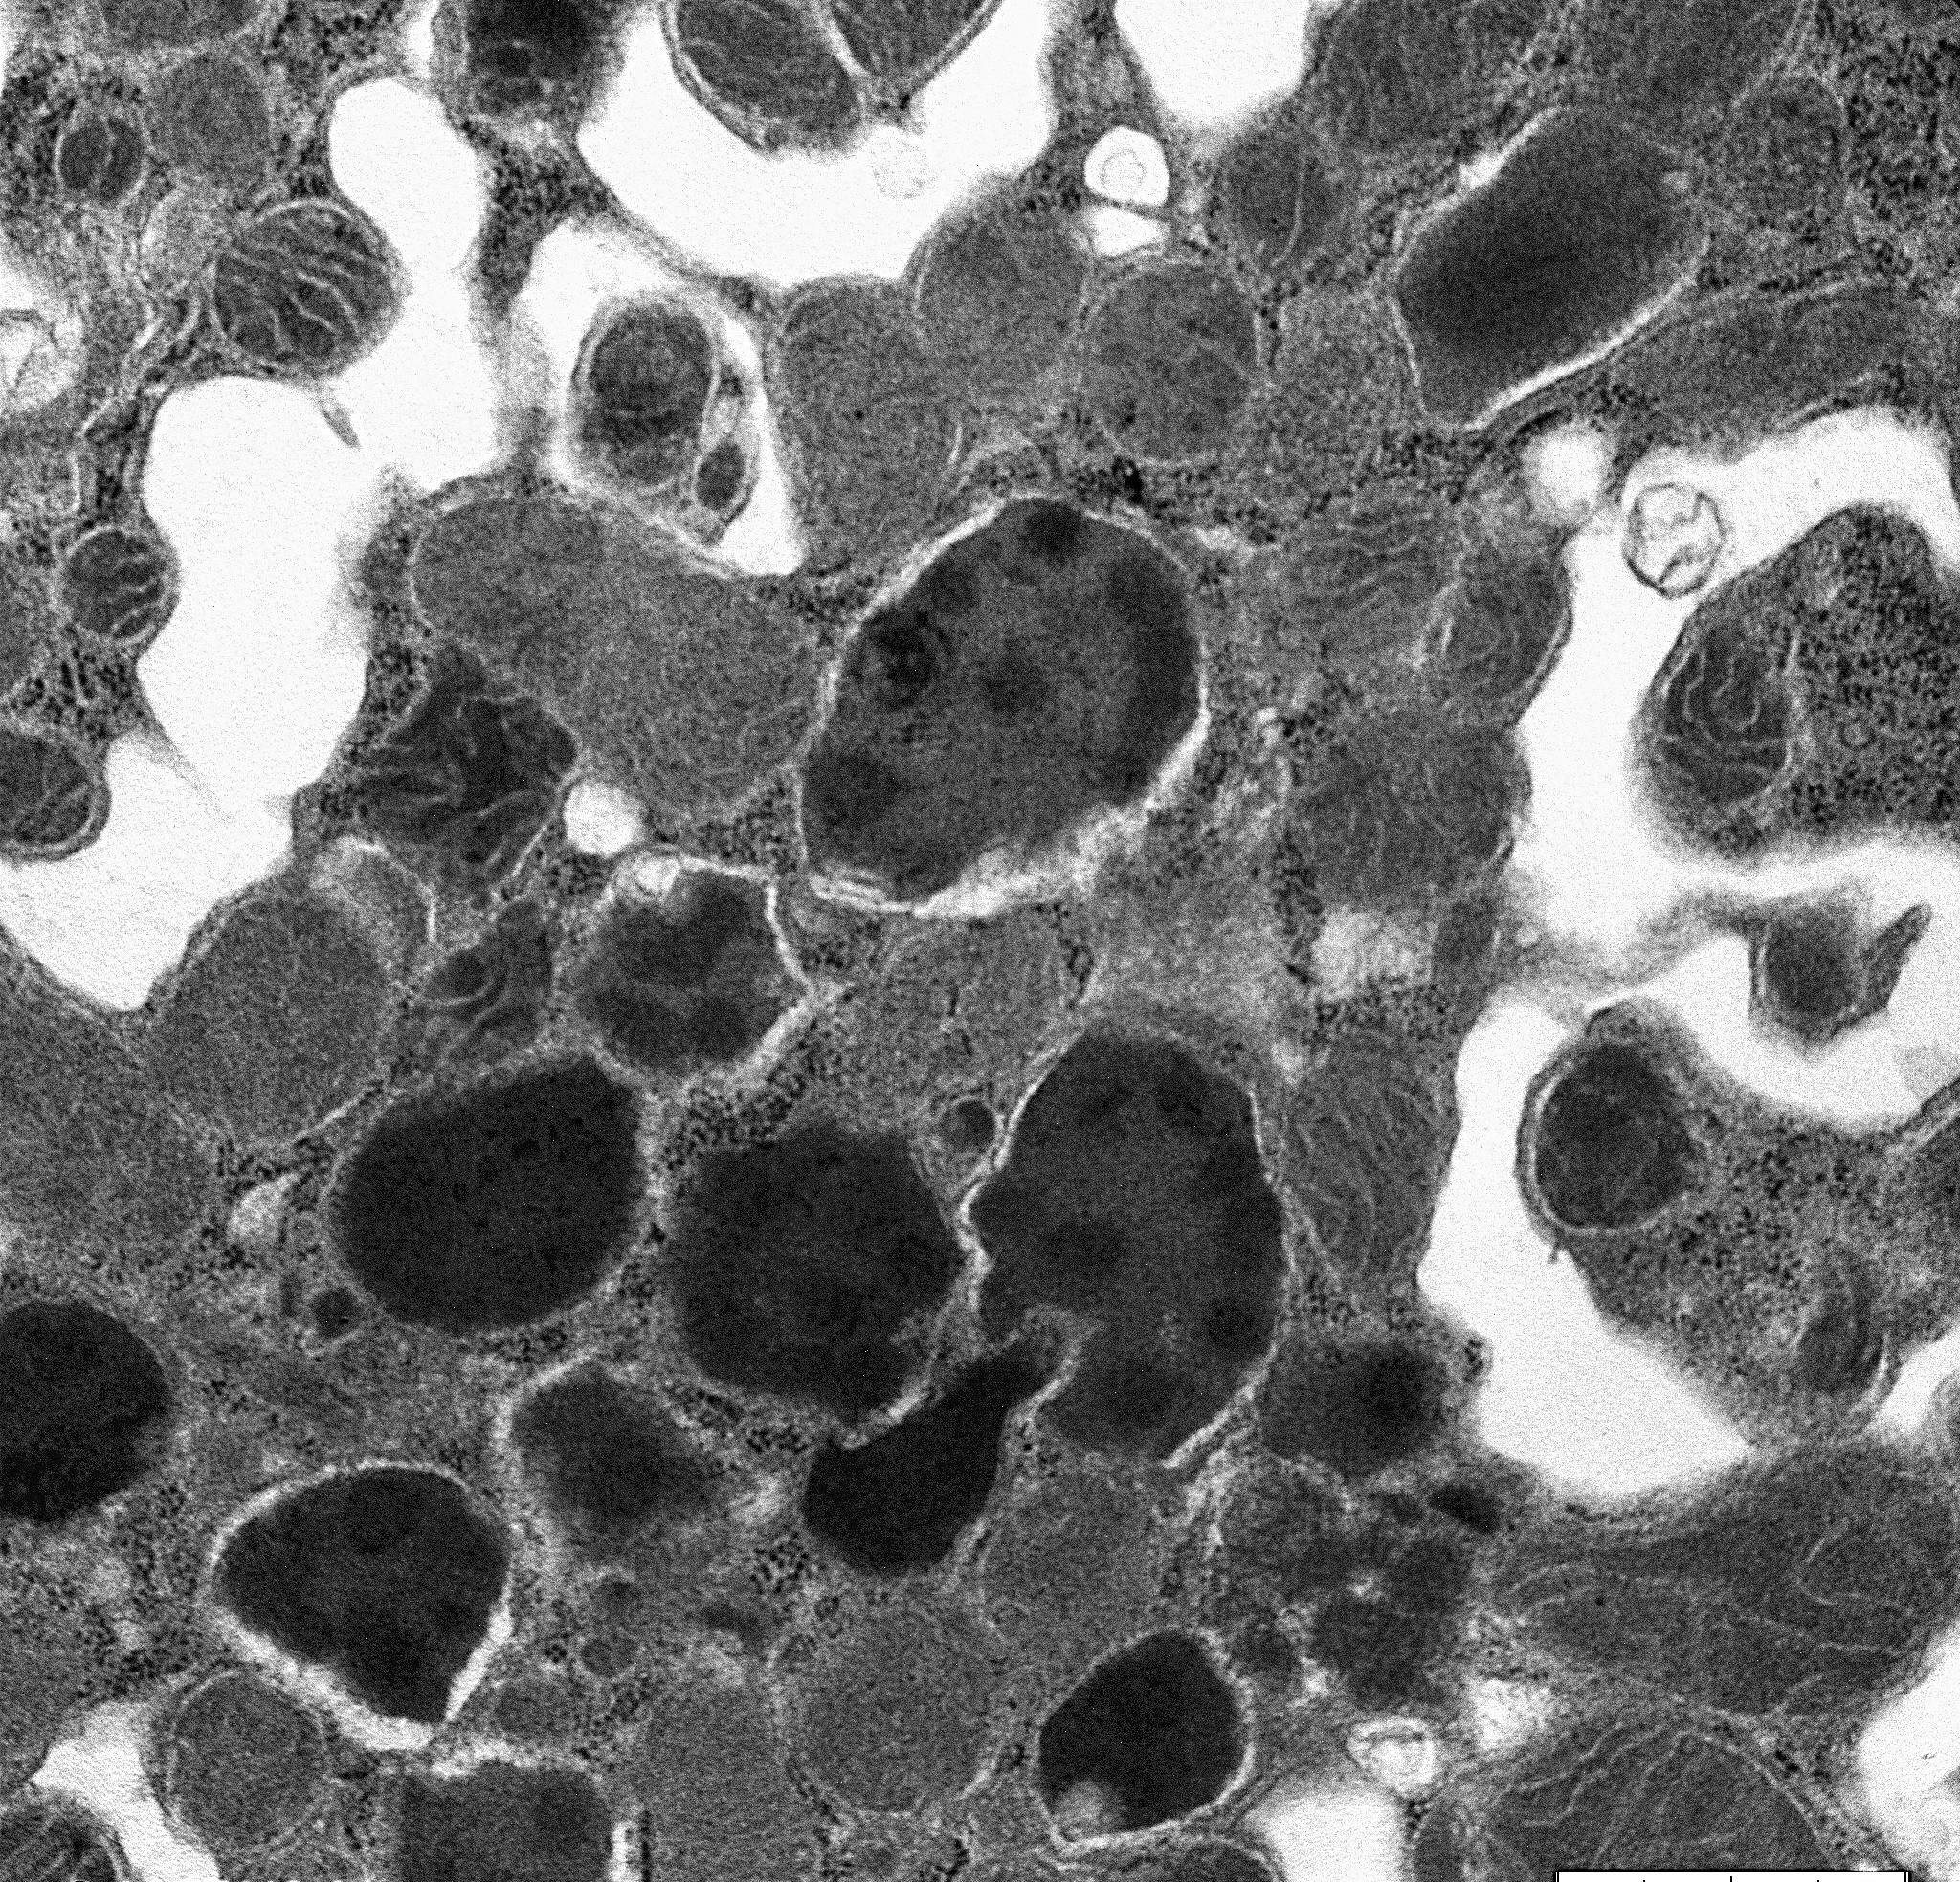

A 71-year-old man with long standing history of hypertension presented with increased serum creatinine of 3.4 mg/dL, detected during routine laboratory examination, with no associated symptoms. He was eventually seen by a nephrologist. A kidney biopsy was performed. The biopsy findings are shown in the following figures (Fig A & B: PASH stain, Fig C: Lambda- immunofluorescence stain, Fig D: Kappa- immunofluorescence stain and Fig E: Electron Microcopy of the proximal epithelial cell cytoplasm).

The diagnosis of monoclonal immunoglobulin deposition disease (MIDD) by renal biopsy often precedes other clinical evidence of dysproteinemia and is commonly the presenting disease, which leads to the discovery of multiple myeloma. The renal diseases most frequently associated with multiple myeloma/MGUS include; amyloidosis, light chain deposition disease (LCDD) and light chain cast nephropathy (LCCN). Less frequently reported is a light chain proximal tubulopathy (LCPT) characterized by kappa-restricted crystal deposits in the proximal tubular epithelial cells cytoplasm. These patients classically present with Fanconi syndrome in the setting of smoldering myeloma. Light chain proximal tubulopathy without crystal formation, on the other hand, is relatively rare and under recognized dysproteinemia related entity which by light microscopy shows nonspecific pattern of acute tubular injury with no significant casts or crystal formation (Fig A and B). However monoclonal staining of protein resorption droplets within proximal tubular epithelial cells, by immunofluorescence, provides clue to the diagnosis (Fig C and D). Electron microscopy shows increased lysosomes with irregular contours and mottled appearance within proximal tubular epithelial cells (Fig E).